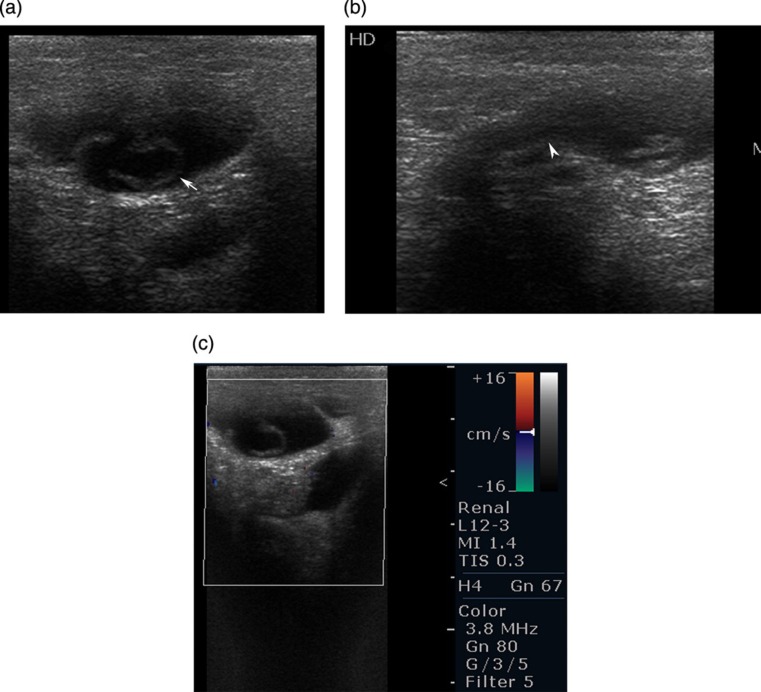

腹股沟管鞘膜积液是一种非常罕见的疾病,它是由于腹股沟管内外翻的腹膜顶骨远端部分形成含液囊而阻塞失败的结果。通常表现为腹股沟无痛性肿胀。超声检查和MRI检查对鉴别腹股沟肿胀有重要作用。我们报告一例5岁女童的影像学表现。

The hydrocele of the canal of Nuck is quite a rare condition and results from the failure of obliteration of the distal portion of evaginated parietal peritoneum within the inguinal canal which forms a sac containing fluid. It generally presents with painless inguinal swelling. Ultrasonography and MRI is plays an important role to differentiate from the other conditions presenting with inguinal swelling. We present the imaging findings of a case in 5-year-old girl.